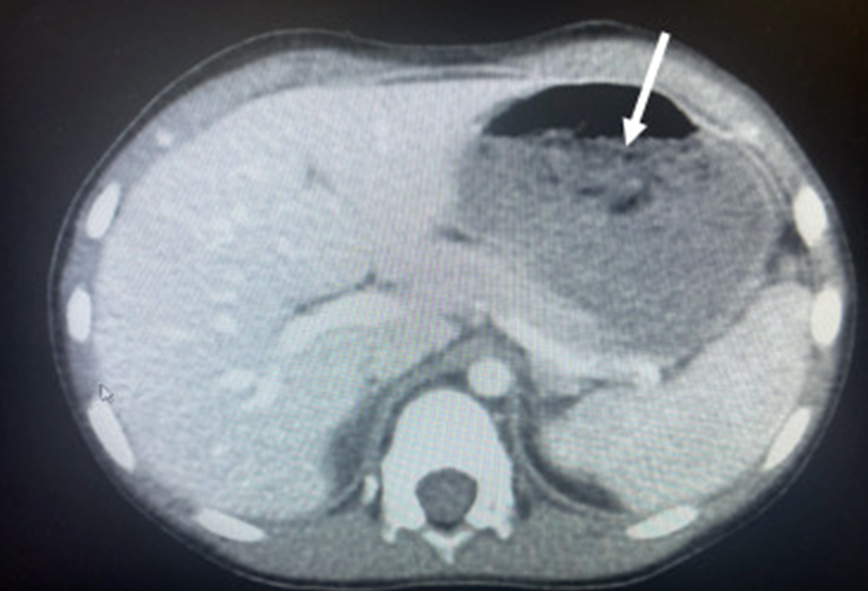

Η ομάδα των γιατρών, με επικεφαλής τον Dr. Chizite Iheonunekwu της Cleveland Clinic, ανακάλυψε το περιεχόμενο στην κοιλιά του με ακτονογραφίες, οι οποίες αποκάλυψαν τη μεγάλη μάζα.